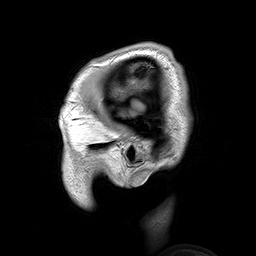

MRI للرأس هو أحد تقنيات الطب النووي التي تستعمل بكثرة في مجال طب الأمراض العصبية.